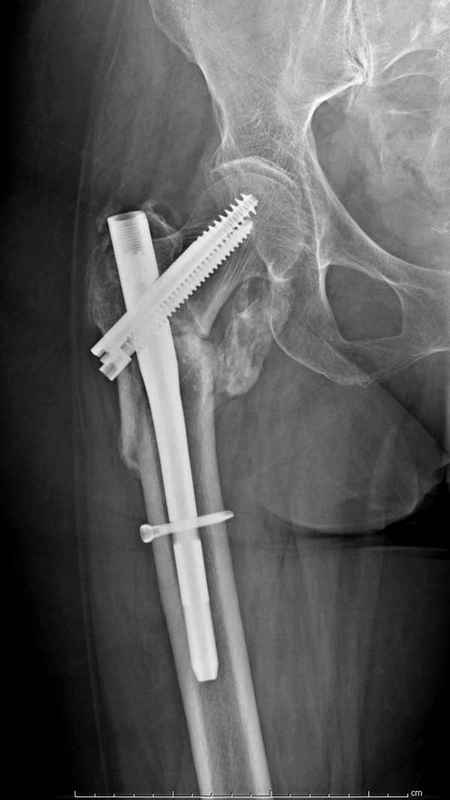

Здесь 83 года, травма в результате падения

Из фиксаторов, мы бы применили цефаломедуллярные, потому что они "по закону моментов" из-за короткого рычага от центра головки к диафизу и по принципу "головка диафиз" механически лучше выдерживают нагрузки, чем пластины.